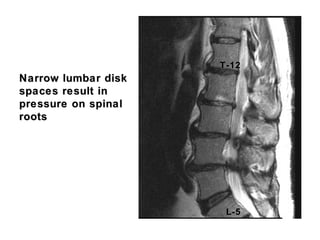

Narrow lumbar diskNarrow lumbar disk

spaces result inspaces result in

pressure on spinalpressure on spinal

rootsroots

L-5

T-12